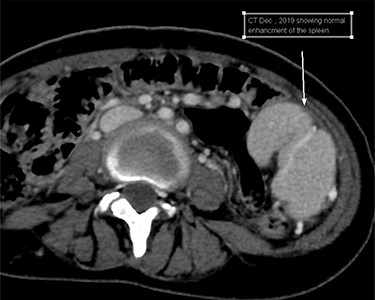

Upon reviewing her file, she had a CT scan done two years prior to this presentation for an abdominal pain and it confirmed the diagnosis of WS; however, no treatment options were offered to her with no follow-ups (Fig. 2).

Cross-sectional image at the time initial diagnosis shows normal enhancement.